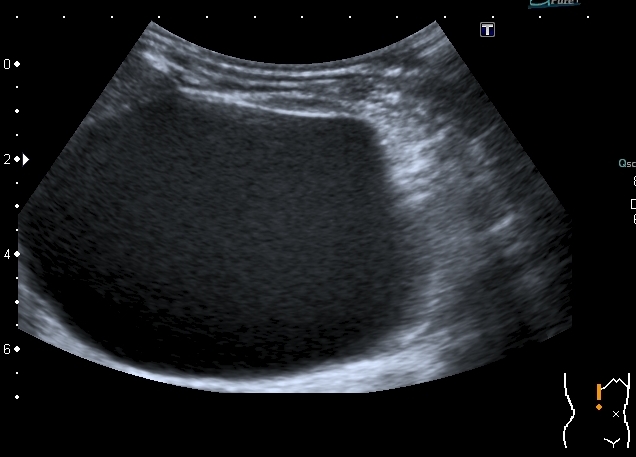

Ещё картинки гидронефроза у ребёнка 6 - ти месяцев, спутать такой гидронефрозище с синусной кистой сложно, а вот с кистой брюшной полости - запросто

Сканирование высокочастотным датчиком  - резидуальная паренхима